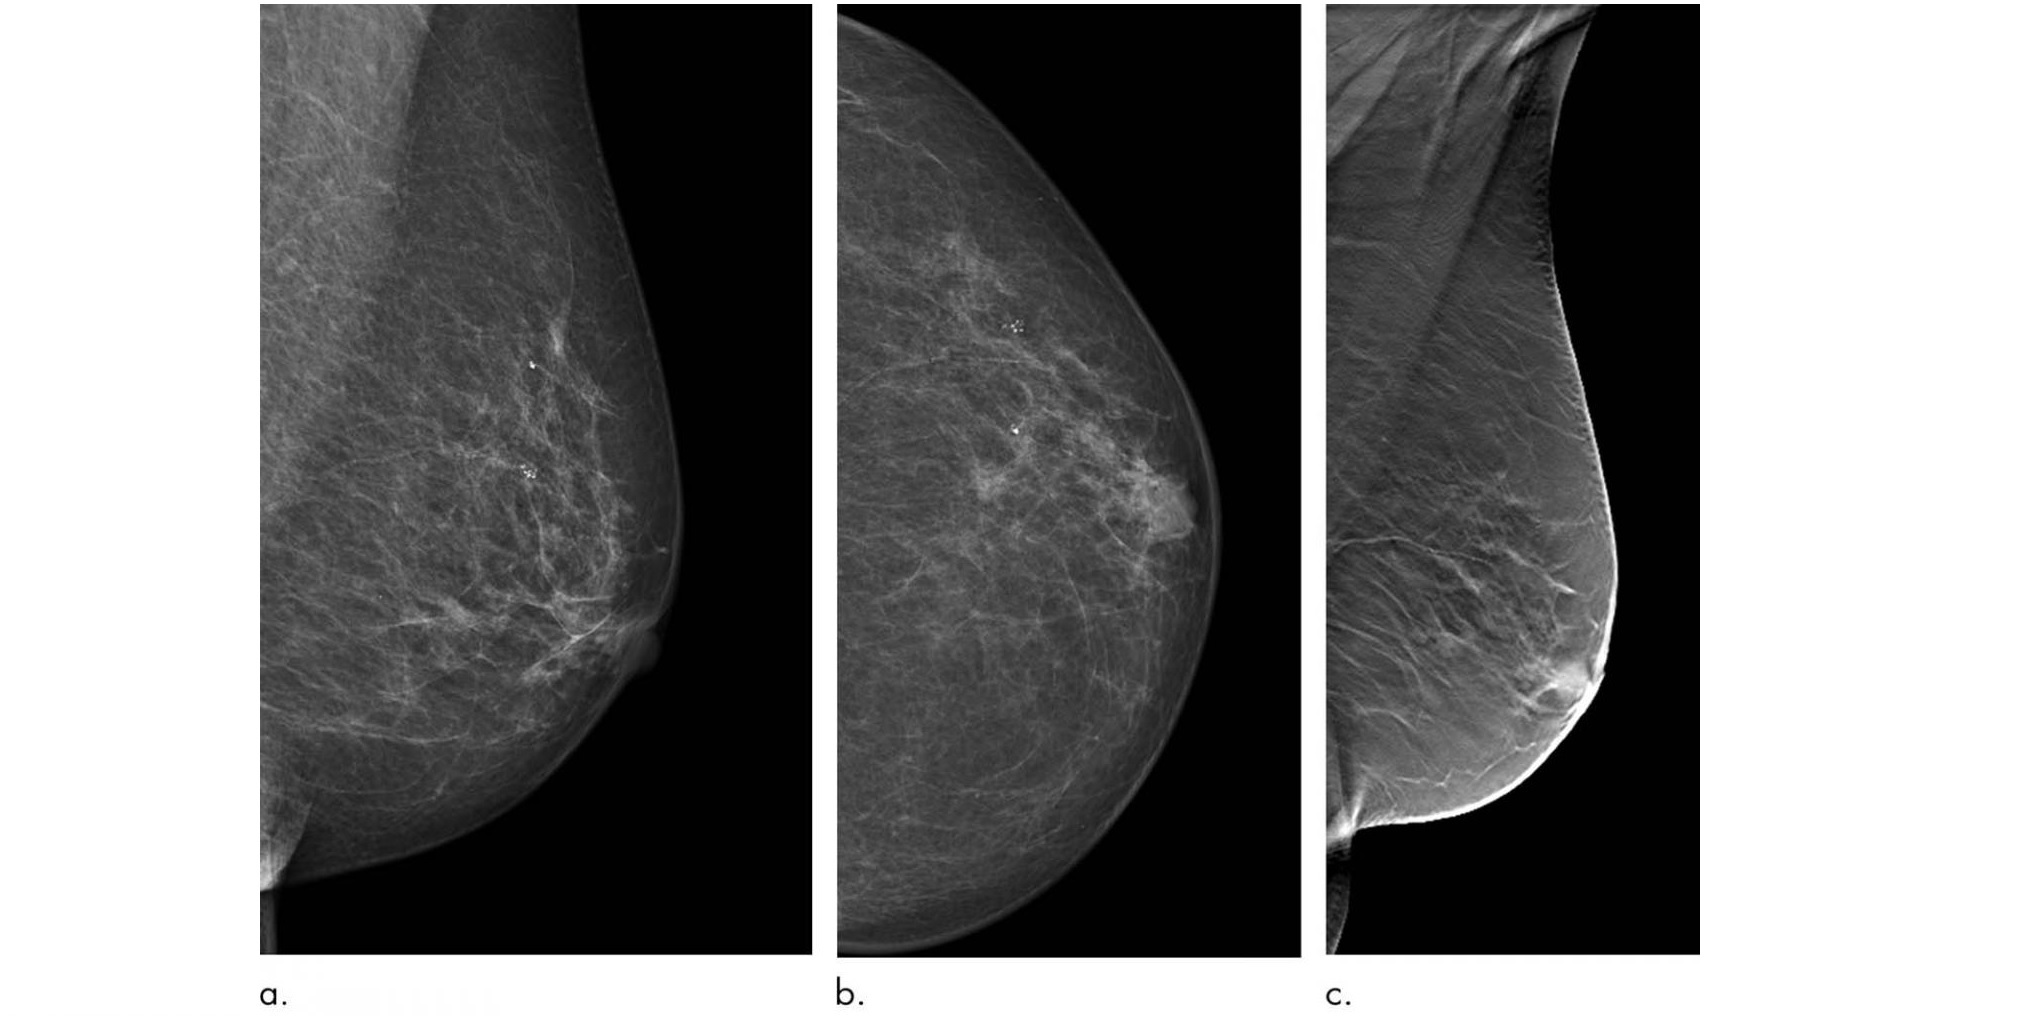

DBT works by capturing a series of X-ray images of the breast from different angles. Previous research has shown that it has a higher sensitivity for breast cancer detection than digital mammography.